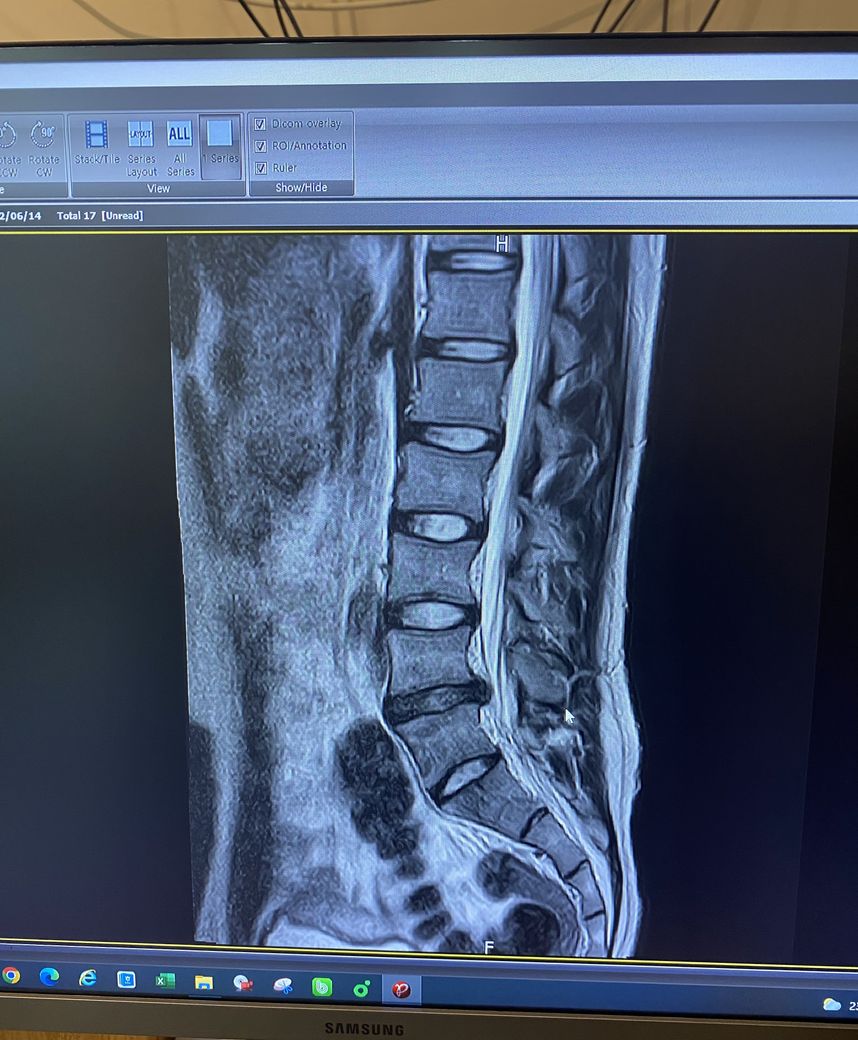

허리디스크 판정 후 6개월동안 침상안정을 취하고 오늘 처음 mri를 찍었습니다.

Mri상 퇴행 및 허리디스크 진행이 심한지?

현재 요추 4-5번 디스크 탈출증으로 인한 방사통이 있으신것 같습니다.

• 올리신 MRI 사진의 소견으로 보았을 때에는 돌출형으로 디스크가 있으며 신경을 꽤 누르고 있습니다. 축영상을 보아야 더 정확한 판단을 내릴 수 있을 것이지만, 증상이 방사통만 살짝 있을 정도라면 경미한 편이며 헬스를 하는 것에 크게 문제될 것 없습니다. 무리가 가지 않는 선에서 헬스와 같은 코어 근육 강화 운동을 해주어서 허리의 부담을 줄이고 디스크 회복을 시도해보시길 권고드립니다.

L4-L5 사이에 디스크 탈출증이 관찰됩니다.

단면도 함께 봐야 정확한 상태를 파악하는게 가능하지만 이 영상만 봐도 상태가 좋지 않음을 알 수 있습니다.

다른 부위의 디스크는 하얀색으로 보이는데 L4-L5 디스크는 색이 많이 검정색으로 보이는것도 수핵이 빠져나갔음을 알 수 있습니다.